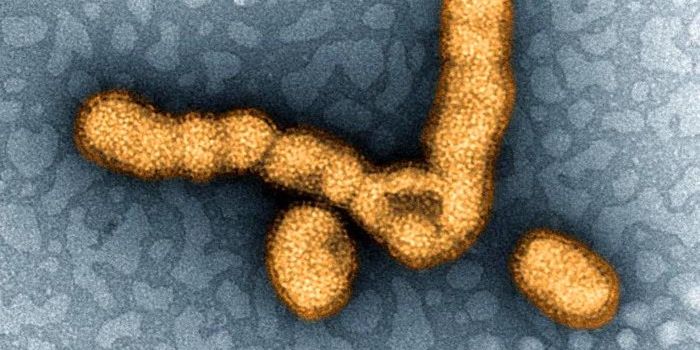

MAY 25, 2021MicrobiologyThough suspected outbreaks have been documented since 1878, the first confirmed outbreak of bird flu, a highly pathogeni ...

APR 04, 2021MicrobiologyThere are many different influenza viruses, which cause from 290,000 to 650,000 deaths every year. That range depends on ...